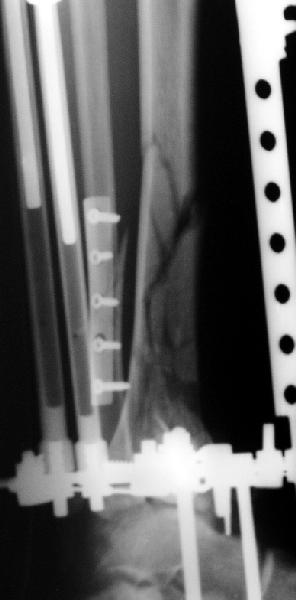

Re: Открытый оскольчатый внутрисуставной перелом д

Возможный альтернативный способ : накостный остеосинтез м/берцовой кости, открытый чрескостный остеосинтез эпиметафиза б/берцовой кости.